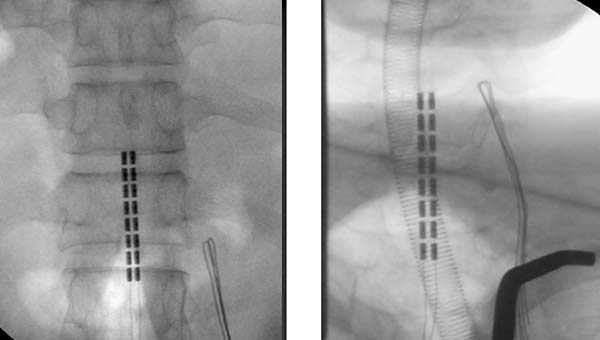

马立新团队经详细检查和评估,决定为这位患者实施“时空序列脊髓电刺激SCS+外骨骼机器人”的创新治疗方案。手术在术中电生理辅助下,精确植入电极于T11-L1/C4-T1节段,术中电生理确定不同电极与右下肢及上肢肌肉对应关系,术后通过编程时空序列脊髓电刺激SCS,结合机器人外骨骼步态训练,实现"刺激激活肌肉-机器人辅助运动"的主动与被动康复联合模式,最大限度恢复运动功能。

胸腰段和颈段电极